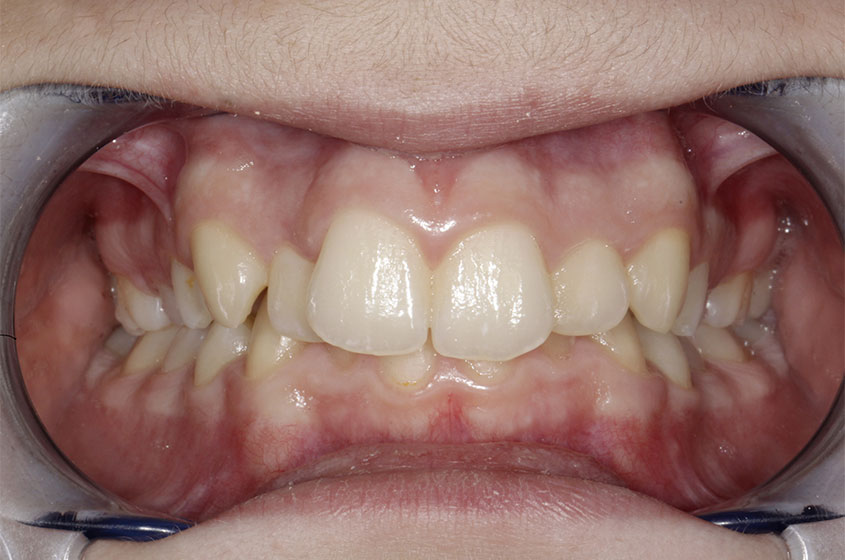

https://sorridibene.etweb.it/wp-content/uploads/2020/07/1.jpg

Morso aperto anteriore

Quando i denti superiori non incontrano i denti inferiori sarà complicato mordere, deglutire, ma anche pronunciare corrett...